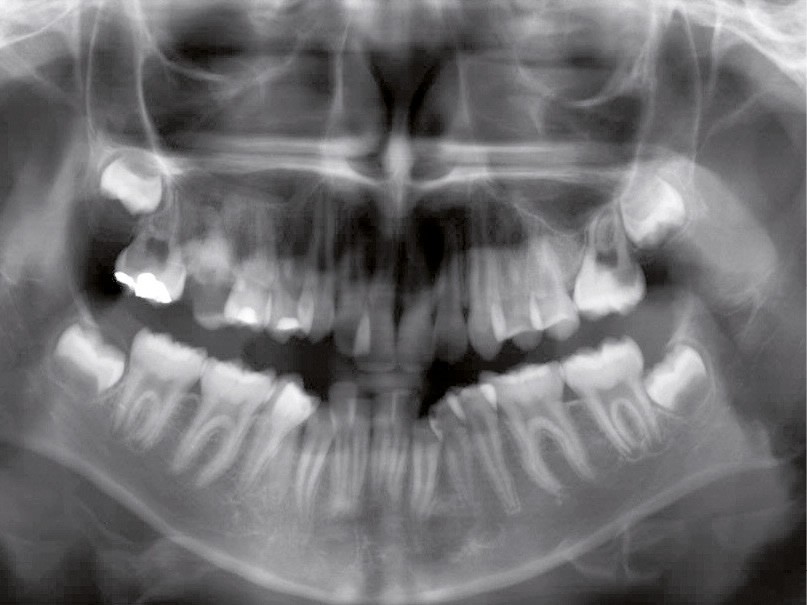

Le niveau d’hygiène est alarmant, car le rituel du brossage des dents n’est pas instauré dans la famille. Des caries se sont développées sur les dents temporaires et en ont imposé l’extraction. Les molaires permanentes ont dérivé mésialement, réduisant l’espace disponible sur l’arcade.

En denture adulte, la DDM est majeure avec un déficit de place estimé de 13 mm à la mandibule. Les lésions carieuses ont aussi touché les premières molaires permanentes maxillaires. La 26 a été avulsée et la 27 a pris sa place. Côté controlatéral, la 16 est fortement délabrée, rendant impossible sa conservation. Les molaires ayant plus mésialé à l’arcade mandibulaire, les rapports occlusaux sont de classe III. Les incisives sont versées vers l’avant, mais nous pouvons considérer qu‘il s’agit d’une biproalvéolie ethnique. Du point de vue squelettique, le patient présente une classe II squelettique par rétromandibulie sur un schéma facial hyperdivergent (fig. 1a-j).